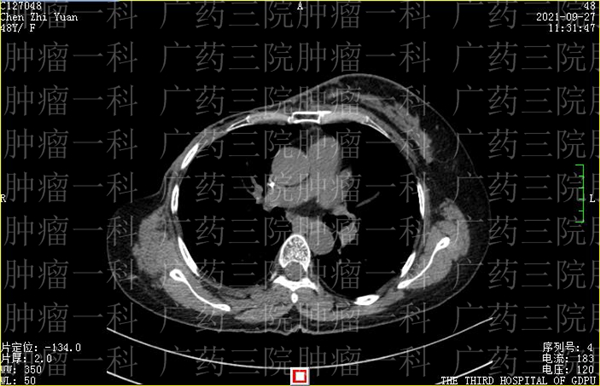

陈女士在2019年发现乳腺非特殊性浸润性癌后,进行了乳腺癌根治术。去年11月,陈女士在复查时,发现肿瘤出现了复发,为了控制病情,延长生命,她来到广药三院肿瘤一科,找到了彭齐荣教授。

经过会诊讨论,彭齐荣教授、刘跃军主任与诸位医生一起,为陈女士制定了微创灌注栓塞+增强免疫治疗方案。